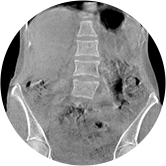

• 腰椎

三維脊柱應用

精準診斷

手術方案規劃

術后隨訪

• 脊柱評估

傳統方法都是在二維平面,依靠棘突或椎弓根相對于椎體的偏移來評估脊柱側凸。WR-3D可以更精準評估脊柱側凸,制定手術方案,可以更直觀地顯示和量化椎體的平移和軸向旋轉,術后評估更準確客觀。

• 全身姿態評估

WR-3D能提供一種負重位狀態下全身的姿態和三維空間任一平面平衡評估,使全脊柱術后評價更客觀、真實 。通過各種臨床參數包括骨盆、脊柱參數評價骨盆、脊柱平衡,避免由于髖膝屈曲造成的代償性脊柱失衡的發生,WR-3D提供了三維空間任一平面平衡評估測量方法,可以更加定量地評估手術效果 。